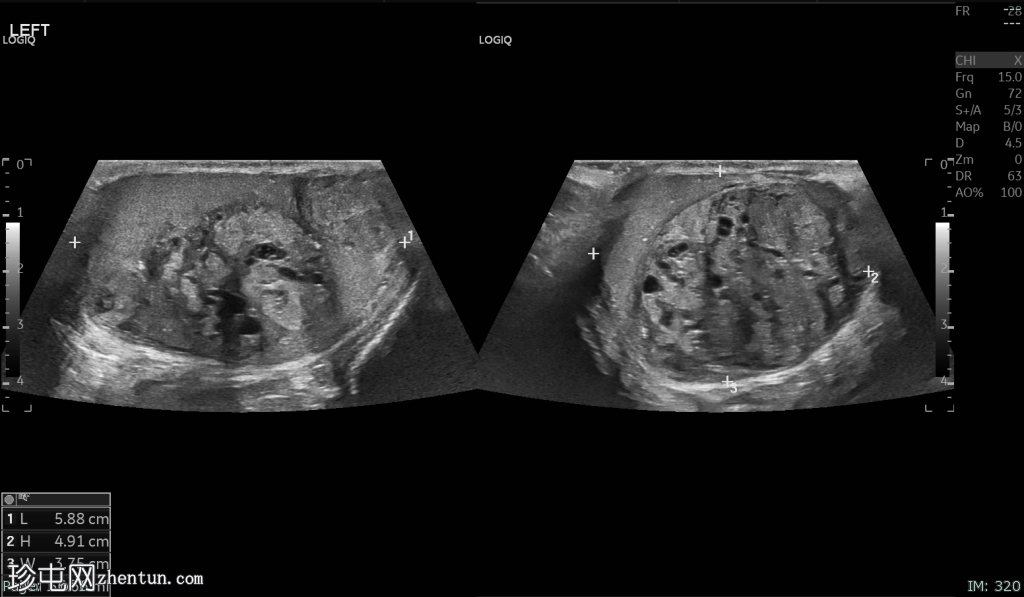

睾丸混合性生殖细胞瘤

左侧睾丸无痛性肿胀2个月。

年龄:20岁

性别:男

超声检查

/ 横切面

2.png

左侧睾丸肿大,体积约56 mL,可见弥漫性微结石,以及三个内部等回声病灶,伴囊性变、微钙化和明显血流信号,最大病灶大小约4.8 x 3.2 cm。

未见腹主动脉旁或髂淋巴结肿大。

CT扫描:未见胸部、腹部和盆腔转移性疾病的证据。

实验室检查结果:乳酸脱氢酶 (LDH):237 IU/L,甲胎蛋白 (AFP):105 IU/L,β-人绒毛膜促性腺激素 (β-HCG):14.2 mIU/mL

患者接受了左侧腹股沟根治性睾丸切除术。

病理报告:混合性生殖细胞肿瘤——畸胎瘤 (60%),胚胎性癌 (30%),卵黄囊瘤“约 5-8%”,疑似精原细胞瘤成分“2%”。